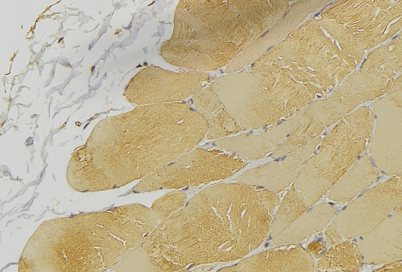

IHC (Immunohiostchemistry)

(Dilution: WB: (1/500 - 1/1000), IH (1/100 - 1/200)Immunohistochemical analysis of PTP1B (pS50) staining in human breast cancer formalin fixed paraffin embedded tissue section. The section was pre-treated using heat mediated antigen retrieval with sodium citrate buffer (pH 6.0). The section was then incubated with the antibody at room temperature and detected using an HRP conjugated compact polymer system. DAB was used as the chromogen. The section was then counterstained with haematoxylin and mounted with DPX.)